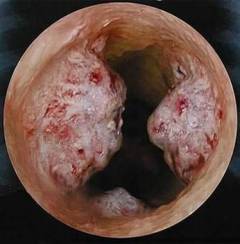

Плоскоклеточный рак пищевода

Плоскоклеточный рак составляет до 95% всех злокачественных новообразований пищевода. Дополнительным фактором риска является злоупотребление горячими напитками и острой пищей, а также гастроэзофагеальная рефлюксная болезнь (ГЭРБ), характеризующаяся забросом кислого желудочного сока в пищевод.

По характеру роста чаще встречается опухолевидная форма плоскоклеточного рака. Опухоль может достигать значительных размеров, вплоть до полного перекрытия просвета пищевода.

Признаками рака пищевода являются:

- Нарушение глотания (дисфагия). Возникает вследствие роста опухоли в просвет пищевода, что нарушает продвижение пищи. Вначале затрудняется глотание твердой, а через несколько месяцев жидкой пиши и даже воды.

- Боли в груди. Появляются на поздних стадиях развития, вследствие сдавливания опухолью близлежащих тканей и органов.

- Срыгивание пищей. Кусочки пищи могут застревать в области опухоли и отрыгиваться через несколько минут после еды.

- Неприятный запах изо рта. Развивается в случае некроза опухоли и присоединения инфекции.

- Кровотечения. Возникают в том случае, если раковый процесс разрушает кровеносные сосуды пищевода (чаще вены), часто повторяются. Проявляется кровавой рвотой и наличием крови в стуле. Данное состояние является опасным для жизни и требует срочной медицинской помощи.